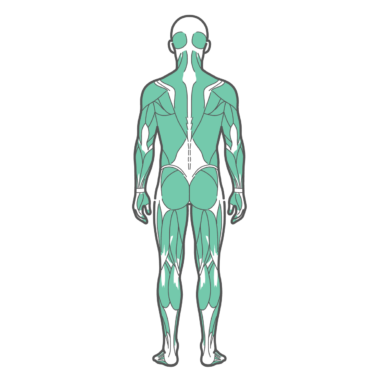

上半身・体幹 男性の全身筋肉図・人体解剖図のイラスト(背面・後ろ姿)